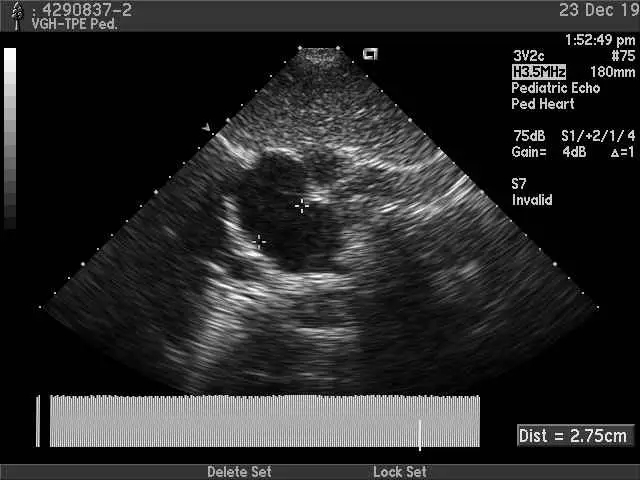

經過一段時間的調整,小妹妹六月中旬回診檢查的結果出來了,原本破洞的直徑從2.75CM變成2.3CM,但是兒科醫師認為沒有變化,是因為0.45公分可能是心臟在超音波檢查時因為搏動產生的量測誤差嗎?可是除了我手底下感覺到結構的改變之外,就小妹妹其他的生理表現,睡眠品質改善、睡姿的變化、排便的狀況、臉色的改變,再再都昭示著這個身體正往好的方向發展,所以、最終的結論是什麼,也許再過段時間、再多些個案,我們就會知道了。